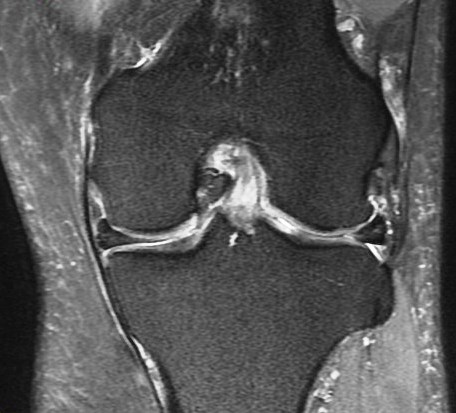

72 y/o M with all over knee pain. No known trauma. R/O meniscus tear.

Root attachment tear of the posterior horn of the lateral meniscus (RID2763)

Much more common to see these medially. These can be mimicked by magic angle but magic angle alone wont result in the irregularity seen here. Also there is some peripheral subluxation of the meniscus suggesting instability. Lateral root tears commonly occur with knee ligament sprains and tears. This patient had a chronic partial tear of the ACL (not shown) Reference article.